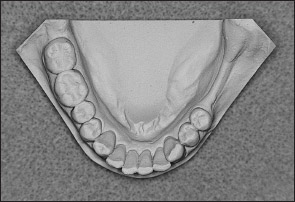

• Kennedy Class I arch: Characterized by bilateral edentulous areas located posterior to the remaining natural teeth (Figs 1-11 and 1-12).

Fig 1-12 Mandibular Kennedy Class I arch.